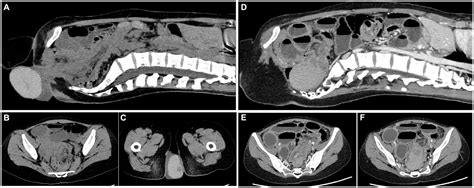

Depending on the initial findings and the suspected severity, your doctor might recommend further tests. One common test is a defecogram, which is a type of X-ray study. You’ll be given a paste or liquid containing barium to swallow or to be inserted into your rectum, which shows up on X-ray. Then, you’ll be asked to sit on a special toilet and have X-ray images taken as you strain and try to pass the barium. This allows the doctor to visualize how your rectum and other pelvic organs function during a bowel movement and can detect rectal prolapse, as well as other issues like rectocele or enterocele.

Other imaging tests might include an MRI of the pelvic floor, which can provide detailed images of the soft tissues and muscles in the pelvic region, offering a comprehensive view of the pelvic floor anatomy and function. Sometimes, a colonoscopy might be done to rule out other conditions, such as polyps or cancer, especially if there’s bleeding or a change in bowel habits that could indicate something else. In some cases, a test called anorectal manometry might be used to measure the pressure and coordination of your anal sphincter muscles, which is important for assessing bowel control. The goal of these diagnostic steps is to confirm the presence and severity of rectal prolapse and to identify any contributing factors, ensuring the most appropriate treatment plan can be devised for you. It’s all about getting the right information to make the best decisions for your health!